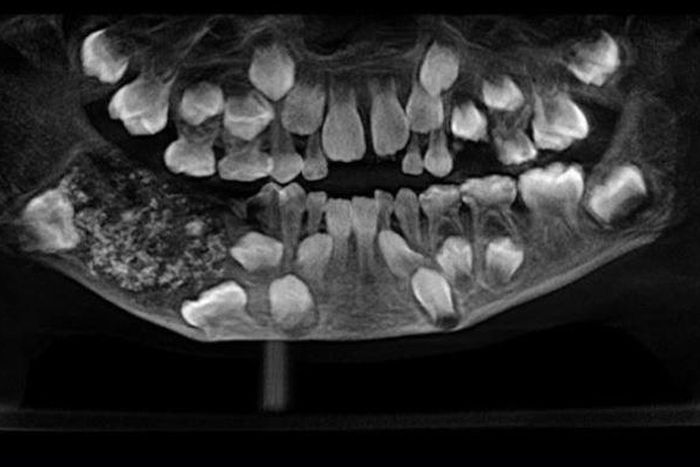

Doctors at the Saveetha Dental College and Hospital in India were surprised to find that a 7-year-old boy brought to their outfit was actually having 526 extra teeth in his mouth.

Reports say the youngster was admitted in July because of swelling and pain near his molars in his lower right jaw.

A team of doctors at the Oral and Maxillofacial Pathology headed by Dr. Prathiba Ramani conducted a scan and spotted a sac embedded in his lower jaw filled with “abnormal teeth.”

It took the team of doctors four to five hours to empty the sac, only to realise that it contained 526 teeth.

“There were a total of 526 teeth ranging from 0.1 millimeters (.004 inches) to 15 millimeters (0.6 inches). Even the smallest piece had a crown, root and enamel coat indicating it was a tooth,” Dr. Prathiba Ramani is quoted as saying.

She explained that the boy was suffering a very rare condition called compound composite odontoma whose cause is not yet known.